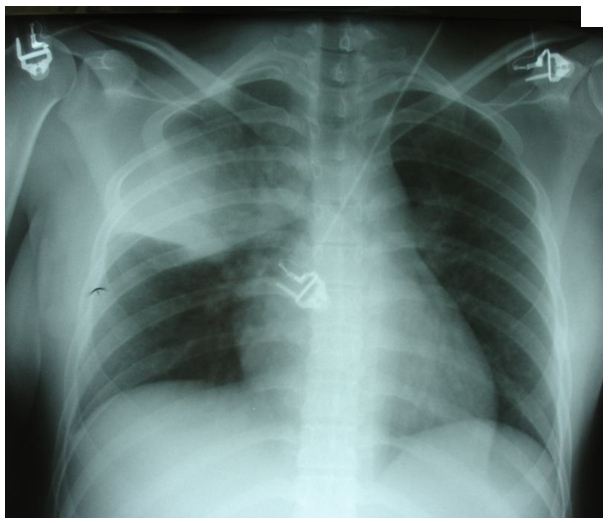

La patiente vous dit que depuis quelques jours elle est enrhumée et que depuis 24 heures elle se sent très fatiguée, essoufflée à l’effort et qu’elle tousse beaucoup. À l’entrée, la patiente a du mal à répondre aux questions. Elle est fébrile à 39 °C. Sa fréquence respiratoire (FR) est à 30/min et la fréquence cardiaque (FC) à 125 bpm. L’auscultation révèle des râles sibilants diffus et des râles crépitants apicaux droits. Le débit expiratoire de pointe est à 43 % de la théorique. La saturation artérielle en oxygène (SpO2) est à 88 %. La radiographie est la suivante. Figure 1.

Question 2 - Comment interpréter la radiographie (une ou plusieurs réponses exactes) ?

Le lobe supérieur droit est ici touché. Deux descriptions de sémiologie radiologique sont possibles. La partie médiale correspond à une image alvéolaire : elle est floue (nuageuse, cotonneuse), mal limitée, avec bronchogramme aérien (bronches toujours ventilées). La partie plus latérale est davantage condensée et renvoie à une atélectasie segmentaire. En effet, l’image est dense, opaque, sans bronchogramme aérien (bronches pleines) et rétractile (scissure attirée vers le haut).

Pour rappel, à l’auscultation, le murmure vésiculaire normal correspond au passage d’air dans les bronches et les alvéoles. Dans le syndrome alvéolaire, les alvéoles sont les seules atteintes, ce qui se traduit par des crépitants (comme des dizaines de petites bulles qui éclatent, bruit de pas dans la neige). La condensation pure est un comblement total des alvéoles avec les bronches toujours ventilées. À l’auscultation, cela se traduit par un souffle tubaire, bruit d’air qui passe dans les bronches, avec phénomène de résonance, car les alvéoles autour sont pleines. À la radiologie, une image dense serait observée comme dans l’atélectasie, mais avec bronchogramme aérien +++. Pour l’atélectasie, les bronches sont pleines donc silence auscultatoire.